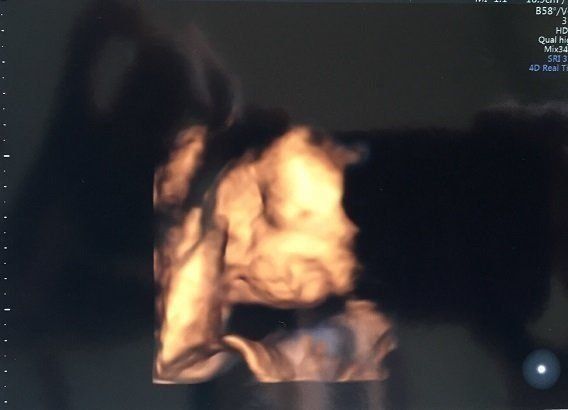

マダムまかろんさんの妊娠28週目のエコー写真 3D画像を撮影することを決意

健診を受けていた病院からもらうエコー画像は、ごく一般的な2Dタイプ。私は、この時期だけの赤ちゃんの姿を記念に残したかったことと、赤ちゃんが本当に元気に育っているのかをはっきりと確認したかったので、3D画像の撮影だけでも予約可能な産院を探すことを決意。この時すでに赤ちゃんがこれ以上大きくなると映りにくくなるというぎりぎりのタイミングでした。

お顔をアップにした4D画像です。うつむき加減で眠っているように見えました。赤ちゃんは順調に大きくなり、これ以降、毎回「ちょっと大きめですね」と言われるようになります。実際、おなかも苦しくなってきて、パソコン作業がつらくなってきました。ちょうど真夏の時期で、外出がとてもつらかったのを覚えています。